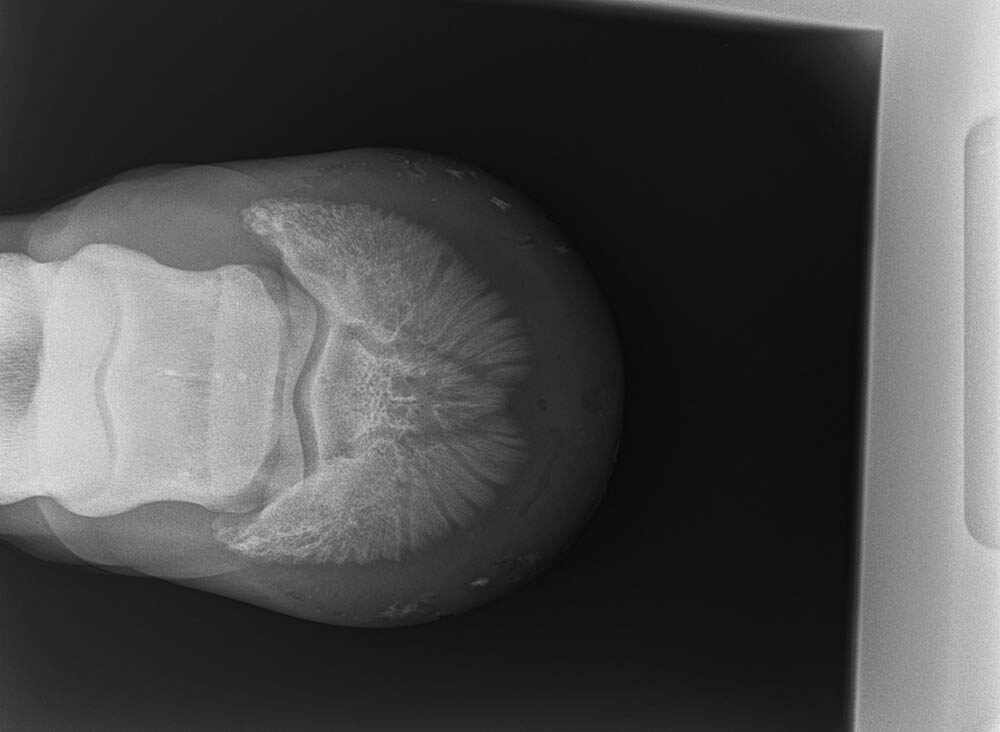

This shows the tip of a nail the farrier tapped to the sole of the foot so we could accurately pinpoint the location of the abscess. © Maxine Brain.

As I had a great relationship with the farrier, we discussed the case and decided the best approach was to work together to find a solution. I was able to X-ray the foot with the farrier present and isolate a small pocket of pus (gas pocket) near the toe of the foot. The farrier was able to cut the tip of a horseshoe nail and fix it to the area of the sole that we both thought approximated the underlying gas pocket. By X-raying again and adjusting our marker, we were able to accurately pinpoint an area and the farrier was able to make a small hole directly over the abscess and allow the pus to escape. The result was a horse that was significantly sounder (and happier) the following day.